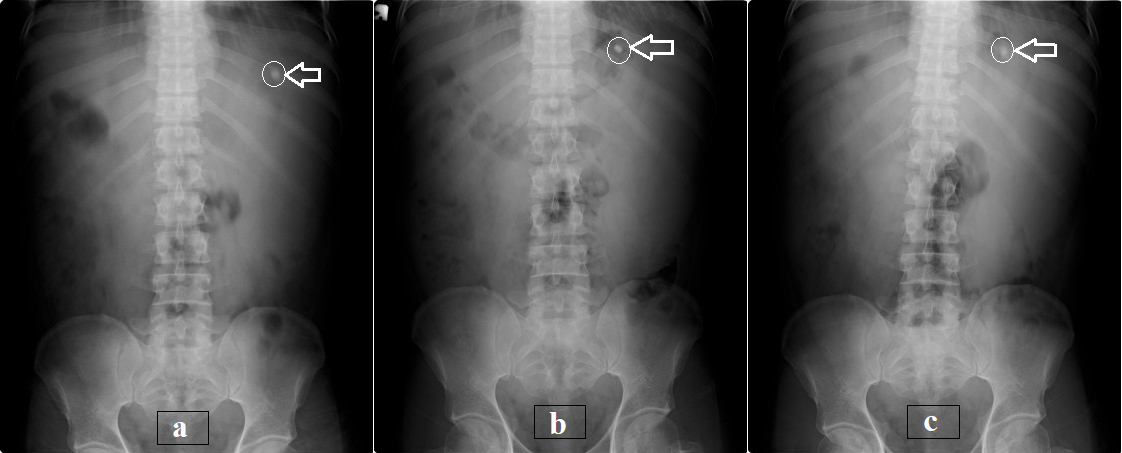

The optimized formulation (F3) was prepared with the same compression force as BaSO4. All the physicochemical properties were within the pharmacopoeial limits [50]. In vivo, radiographic studies were conducted on 3 healthy male human volunteers with a glass of water and a standard diet was provided to find out the GRT of the tablets. X-ray pictures were taken at different time intervals such as 1, 3 and 6 h.

The X-ray image shows that tablets remain in the stomach for about 6 h and which indicate the good floating property (shown in fig. 10). These studies revealed that the mean GRT was found to be 6±0.5 h.

Fig. 10: X-ray images of optimized formulation (F3); a) at 30 min; b) at 3 h; c) at 6 h (tablet position was indicated with the circle and arrow mark); (n=3, mean±SD)